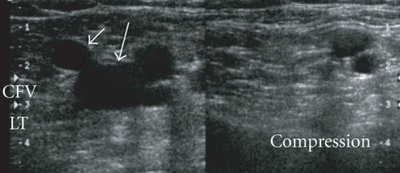

- Each segment of vein identified must be assess as compressible and noncompressible

- Touching of the anterior and posterior walls indicates a normal exam

- No touching with pressures sufficient to deform the artery indicates DVT

Abnormal

A bedside ultrasound was conducted to assess for DVT with clinical indications of edema and pain. The extremity was assessed at 3 locations – common femoral vein, saphenofemoral junction, and the popliteal vein. Sequential compressions at these sites showed a noncompressible popliteal vein. DVT is present at the level of the popliteal vein.

Abnormal Study - Incompressible left Common Femoral Vein